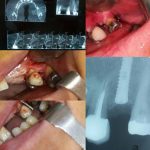

• عکسبرداری و رادیوگرافی از دندان

برای تشخیص میزان و سطح آسیب و همچنین تعیین روش مناسب جهت درمان ریشه دندان، متخصص درخواست عکسبرداری و رادیوگرافی دندان را می دهد.